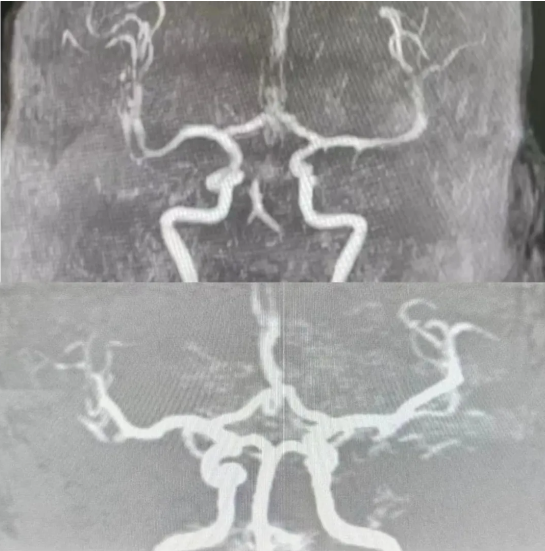

溶栓治疗对比照

由于距离患者发病已经过去了一个半小时,若再拖延,就有可能错过最佳抢救时间。于是,王姗姗当即告知患者家属需进行溶栓治疗的必要性。征得患者家属同意后,立即为患者进行了溶栓治疗,为下一步抢救治疗赢得了宝贵时间。

考虑患者为重型脑卒中,还需桥接经皮颅内动脉取栓术。“立即联系总院!”高彦霞立即与自治区人民医院卒中中心对接,与此同时联系120救护车将患者转至自治区人民医院,接受桥接经皮颅内动脉取栓术,开通血管,彻底打开了“生命通道”。患者在自治区人民医院住院治疗10天后,康复出院。